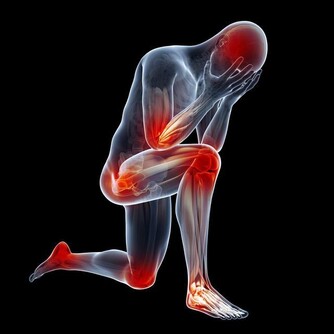

所以,其實奪走很多腎友寶貴生命的罪魁禍首,並不是尿毒症!而是腎病所引發的多種並發症,今天我重點給大家整理出腎髒病並發症排行榜,你不妨猜猜第一位是什麼,隨我來!

第一位,腎性高血壓

有相當一部分人覺得高血壓不是什麼事兒,可是你知道高血壓在加重腎病,引發心腦血管疾病當中的影響力嗎?它可是居於各類腎髒病並發症之首的!

所以即便你的病情比較輕微,也得重視高血壓,如果比較嚴重,更不能擅自停減降壓藥物。

第二位,多種感染

感染是一種常見的並發症,舉例子來說,腹膜透析的患者容易發生腹膜感染,這是極其危險的。還有呼吸道、消化道感染等,都會給腎友們的生命帶來很大威脅。

第三位,高鉀血症

由於腎病患者正常的腎功能出現損害,導致體內的鉀離子不能有效排出體外,隨著鉀離子的逐漸堆積,人體就會出現高鉀血症,引起嚴重的心髒病,進而你的生命也就· ·····

第四位,多種心髒病,例如心梗、心衰

基本上腎病患者的血液都會出現一些問題,而血液問題一直以來都是心臟疾病的元兇之一,所以,一般腎病的並發症當中冠心病、心梗、心衰也比較常見,大家一定要注意預防!